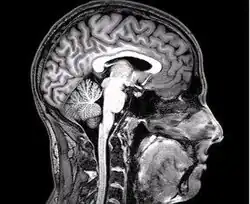

Figure 1: Compassion can be seen neurologically

Although there have been many debates on the actual definition of compassion (Gilbert, 2019), whether it is an emotion or a complex construct, it has been consistently shown that compassion can be shown neurologically (Kim et al., 2020). Through the first meta-analysis conducted on compassion, comprising of 16 peer reviewed articles (Kim et al., 2020), brain activation was found consistent in brain region through across multiple studies. In the meta-analysis Kim et al. used a software called GingerALE which would locate above-chance clustering of the foci between experiments, using an estimation likelihood estimation (ALE) (Laird et al., 2005). This software provided cluster size, location, and anatomic labelling. Although the software could analyse above-chance foci clustering, not all experiments were consistent in their testing measures, this caused the 16 articles to be broken up into subcategories which were then tested against one another for a more accurate reading on brain activation.

ALE had found that seven regions of the brain showed consistent activation across multiple of the studies included in the meta-analysis being the Anterior Cingulate, Bilateral Inferior Frontal Gyrus, Bilateral Insula, Middle Frontal Gyrus, Medial Frontal Gyrus and Basal Ganglia/Thalamus circuitry (Engström & Söderfeldt, 2010; Kim et al.,2020; Mascaro et al., 2012).

Out of the seven regions, two were found to have the most significant activation (Kim et al. 2020). The Anterior Cingulate Cortex and the Anterior Insula. The anterior Cingulate Cortex is responsible for the important cognitive roles, such as decision making and impulse control but has also been determined to play a role in the emotion of empathy (Stevens et al., 2011). The Anterior Insula is geared more towards the breaking down of negative sensory input, this region of the brain, although considered one of the least understood areas, has shown activation during negative visual stimuli (Uddin et al., 2017). These two regions are considered integral parts of the salience network. The salience network is usually tapped into when a person experiences or observes another’s pain (Cao et al., 2017). The activation of these regions was primarily found throughout stimulus tasks, consisting mostly of the presentation of negative stimuli, but was also found through mindset tasks, through tapping into past experiences (Kim et al., 2020).